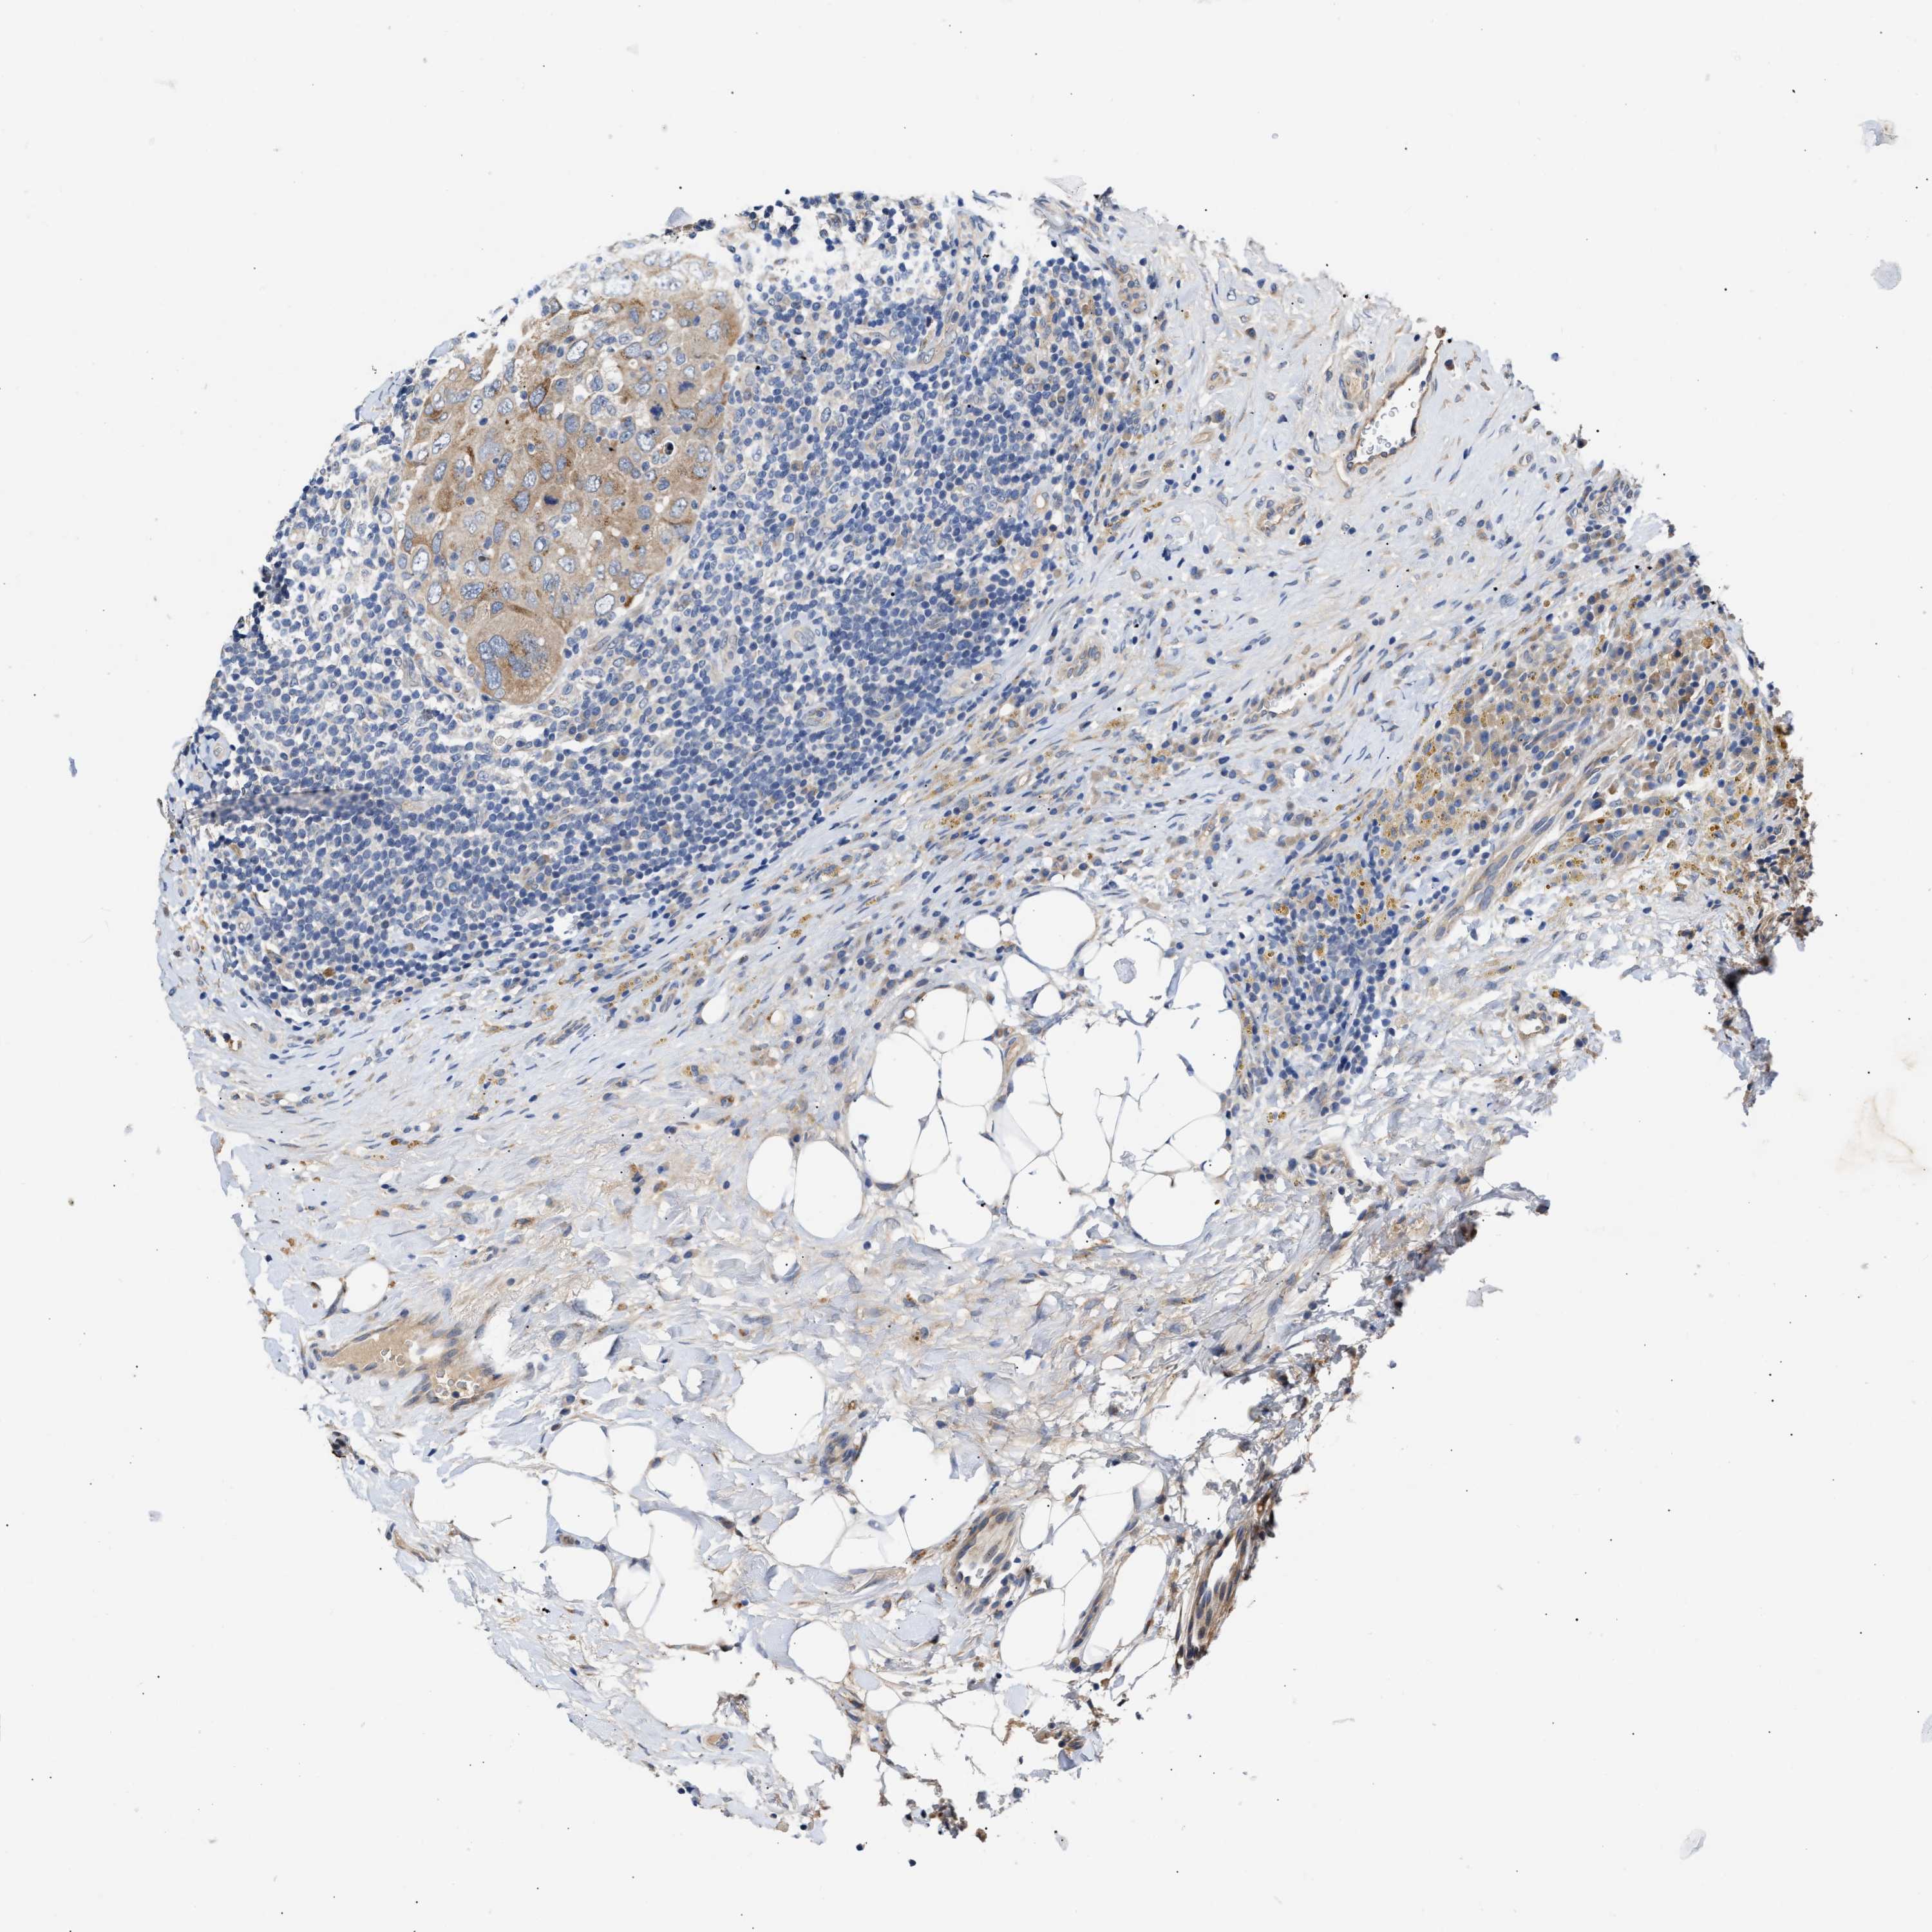

CANCER BREAST CANCER Show tissue menu

BRCA TCGA BRCA VALIDATION PROTEIN EXPRESSION

ANTIBODIES

AND

VALIDATION